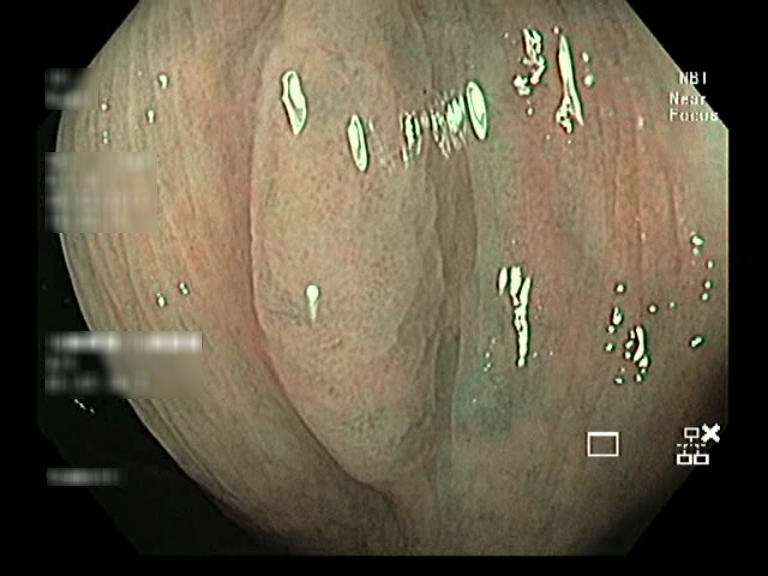

| Lesion | White Light Frame | NBI Frame | White Light Video | NBI Video | Camera Calibration |

| hyperplasic_01 |  |

|

WL.mp4 | NBI.mp4 | cam.xml |